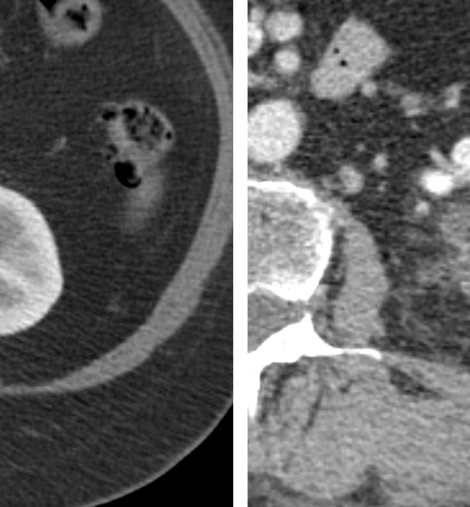

To determine whether patients who required multiple renal ablation procedures to successfully treat an RCC tumor had worse clinical outcomes than patients who were successfully treated with a single renal ablation procedure, researchers completed a retrospective study of all percutaneous ablation procedures performed at a single center from 2004-2022.

They reviewed outcomes of 269 patients and found that while 92% of patients had successful elimination of their RCC in a single ablation procedure, 8% required two or more ablations to achieve complete tumor response.

“For example, a more conservative initial ablation margin might be planned in patients who have impaired renal function or have a tumor located adjacent to critical internal renal structures—such as the collecting system,” he said. “Physicians may be more comfortable with a conservative approach, knowing that a second ablation can be performed if required and won’t impact their final outcome.”